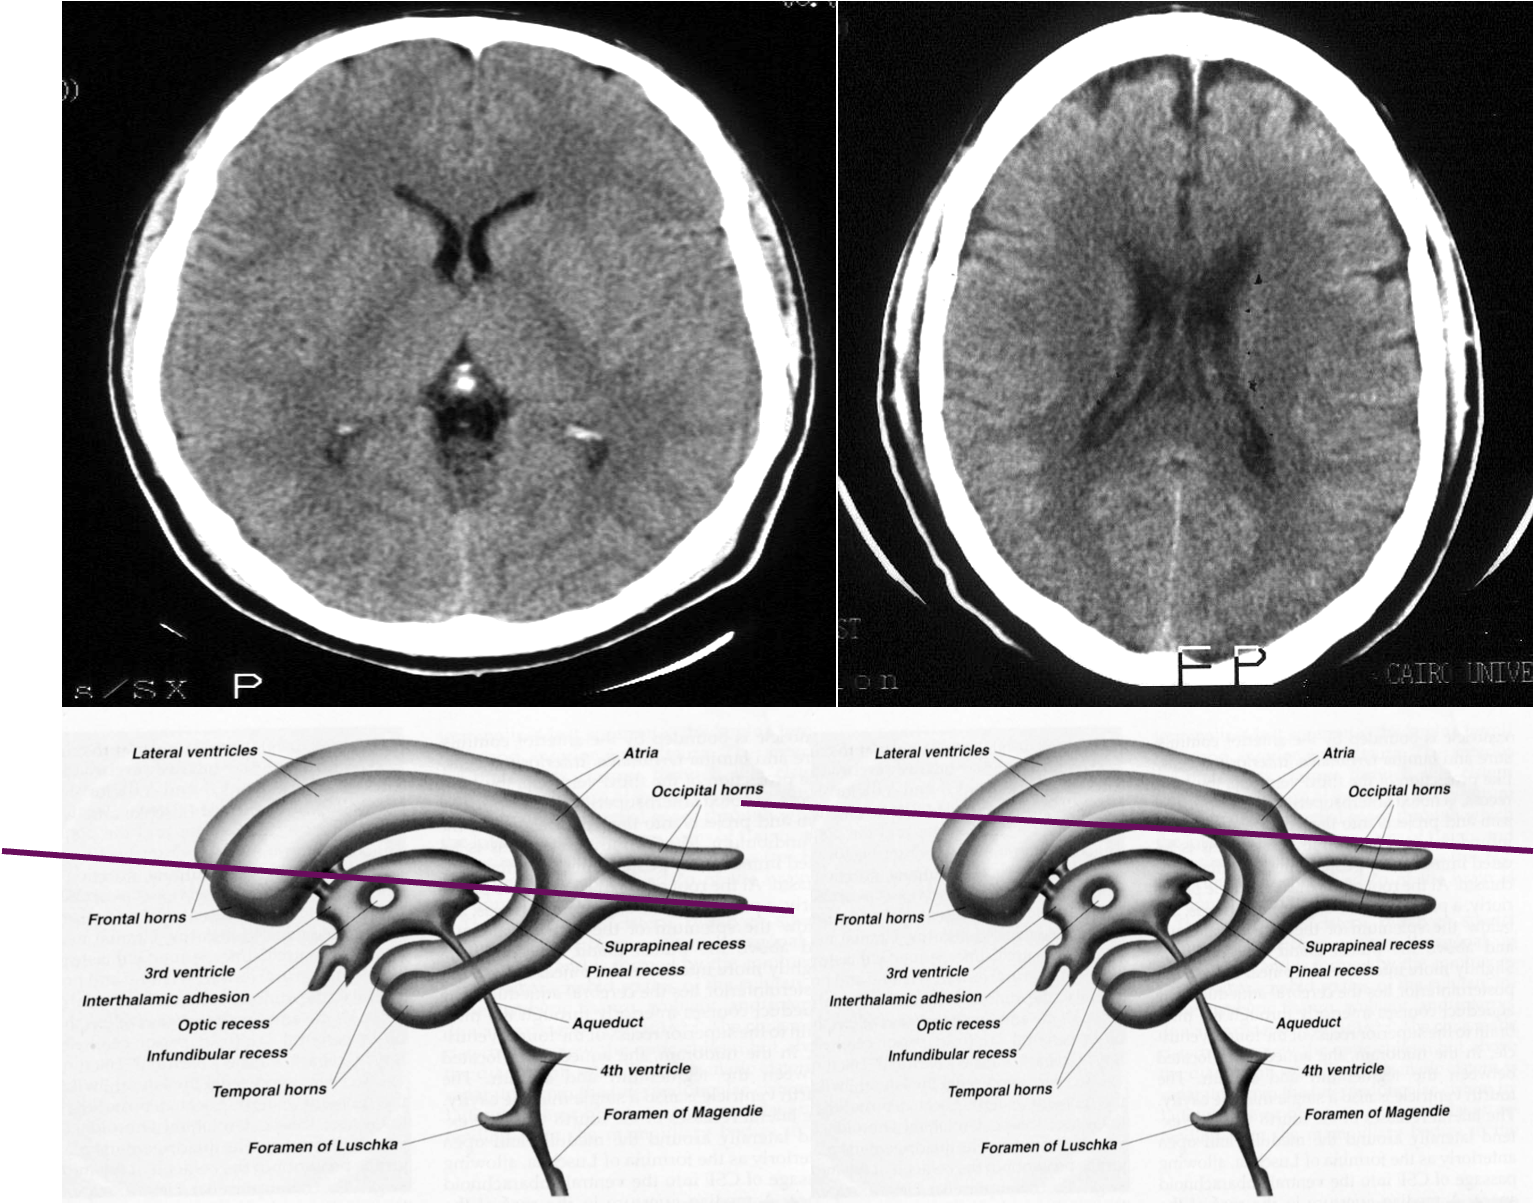

Ventricular anatomy

CT show the anatomy of skull in transverse section